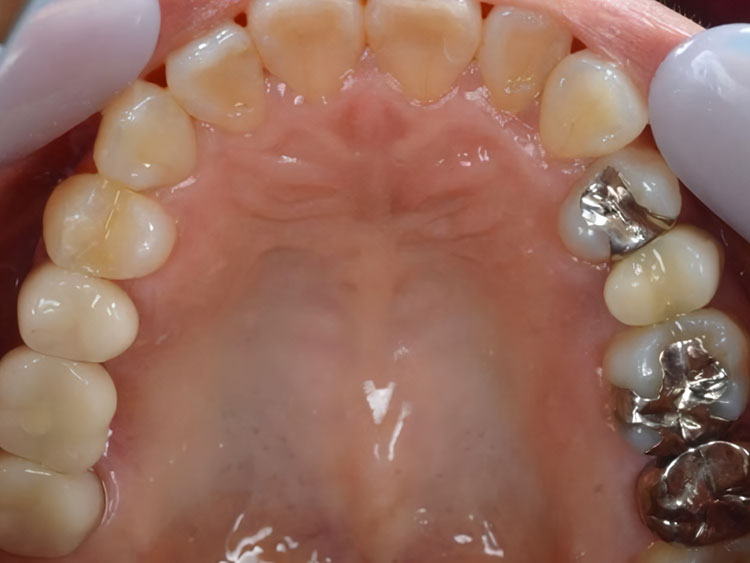

インプラント症例 Case1

Treatment cases

Before

After